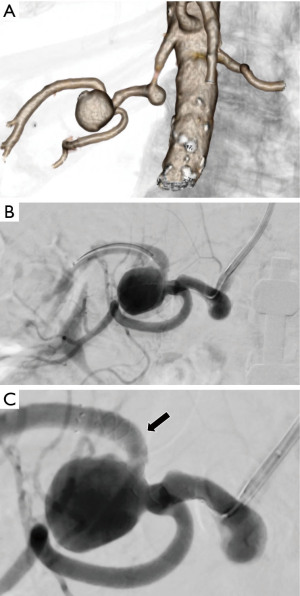

Renal artery aneurysms constitute 25% of VAAs. While commonly linked to hypertension, they have also been associated with connective tissue disorders (53,54). For aneurysms with narrow necks and a saccular shape, the most prevalent endovascular method to isolate the aneurysm and sustain normal blood flow in the main artery is coil embolization. In cases of fusiform renal aneurysms affecting distal branches, embolization using coils or liquid embolic agents can be performed with minimal acceptable loss of parenchyma due to limited collateral formation (55). For aneurysms with wide necks, viable endovascular alternatives include covered stents or stent/balloon-assisted coil embolization, which can simultaneously isolate the aneurysm and maintain renal blood supply (56). Recently, neuro-interventional devices and flow-diverting stents have been utilized with promising outcomes (57) (Figure 5).